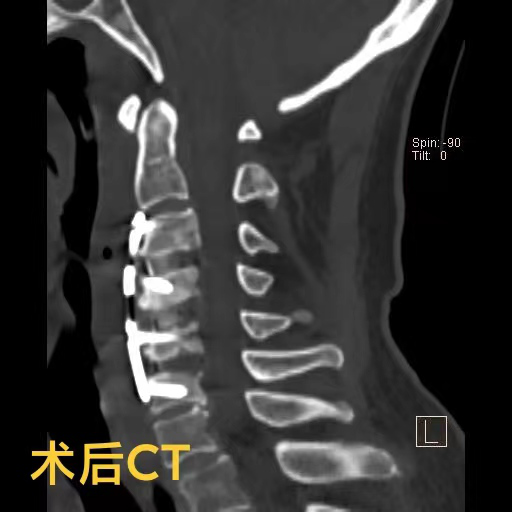

羅醫生第一時間聯系了神經外科脊柱脊髓組的鄧雷主治醫師。針對陳爺爺及其家屬的擔憂,鄧雷主治醫師進行了耐心細致的溝通,最終陳爺爺決定配合醫護進行手術治療。患者高齡且有基礎疾病,手術方案需要慎之又慎。神經外科副主任(主持工作)徐忠燁主任醫師組織全科醫生根據患者具體病情,制定了最終方案:前路3節段頸椎間盤切除+頸椎后凸畸形矯正。

陳爺爺長期的頸椎變形產生了大量骨質增生,給術中的鄧雷、蔣登志醫生出了難題。在神經顯微鏡下,他們的眼睛如鷹,指尖之中飛舞最溫柔的神經刀鋒,雕塑著最堅硬的頸椎驁骨。最終,手術耗時兩個半小時,成功矯正,沒有神經損傷!患者術后3天康復出院。